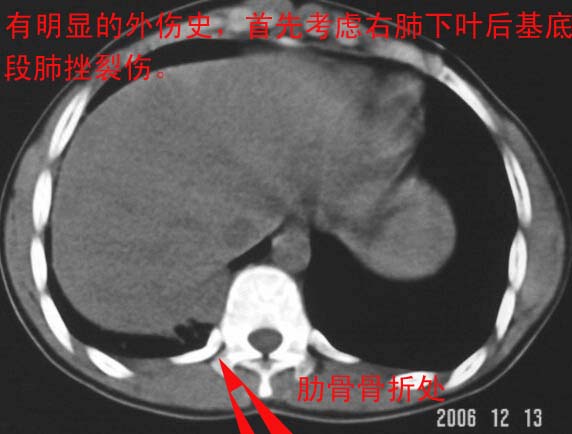

最后一幅图像病灶区可分椎旁肋骨骨折可能?请示骨窗,结合外伤史考虑右下肺挫伤。

最后一幅图像示椎旁肋骨走形欠自然,请示骨窗,结合外伤史考虑右下肺挫伤。

支持肋骨骨折,肺挫裂伤。